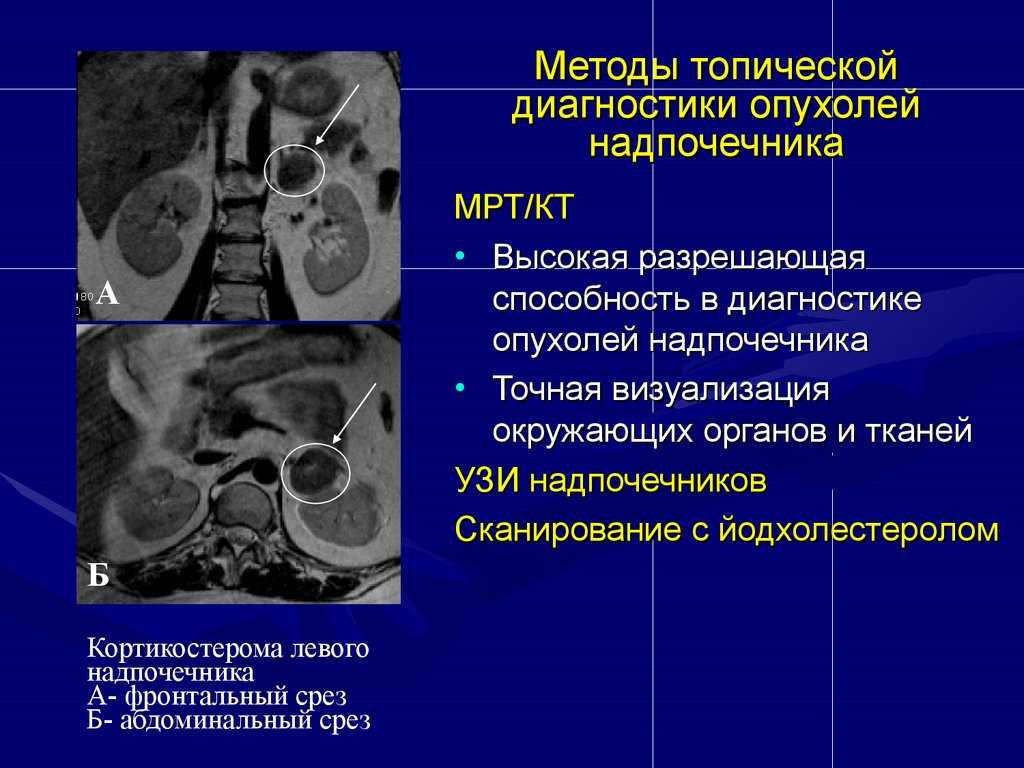

Лимома Беркита Тип злокачесивенных клеток. Клетки Березовского-Штернберга морфология. Ходжкинская лимфома морфология. Цитологическая картина лимфомы Ходжкина. Кт при опухоли надпочечников. Кортикостерома надпочечника кт. МСКТ объемное образование надпочечника. Кт мрт аденома надпочечника.

Кт при опухоли надпочечников. Кортикостерома надпочечника кт. МСКТ объемное образование надпочечника. Кт мрт аденома надпочечника. Опухоли задней черепной ямки. Объемное образование задней черепной ямки. Опухоли задней черепной ямки клиника.